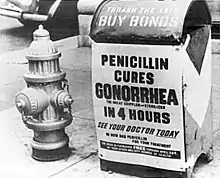

The world's first antibiotic, penicillin, is produced by a strain of the mold Penicillium rubens (formerly Penicillium chrysogenum). Though the history of penicillin is centuries long, Scottish physician Alexander Fleming is usually credited with initiating the modern era of penicillin discovery, research, and development when he found the mold (Penicillium notatum, now also P. rubens) growing on a culture plate in his laboratory in 1928. Penicillin is effective on gram-positive bacteria. The antibiotic-producing strains of Penicillium in the early years produced relatively low yields of unstable penicillin. The yields were so low that urine from treated patients was collected and the penicillin remaining extracted and reused. At Oxford University in England a team including Dr. Howard Florey, Dr. Ernst Chain and Norman Heatley took up the goal of finding solutions to penicillin recovery issues. After a referral on who best to contact about increasing production, Florey and Heatley secretly came to Peoria Illinois on July 14, 1941, with their penicillin producing mold. WW2 necessitated moving of the work on penicillin to the United States where industrial supplies were not as constrained for the war effort. They met with personnel at the USDA (then Northern Regional Research Laboratory, NRRL, now National Center for Agricultural Utilization Research, NCAUR). There at the "Ag Lab" corn steep liquor, a byproduct of alcohol production, had been used for growing mold cultures in the past. It was found out later that phenylacetic acid, a side chain precursor of penicillin was present in quantity in the liquor and had increased yields. Other additions to the growth media such as lactose(milk sugar) were restricted during the war for penicillin production. Major breakthroughs at the Ag Lab came in the years between 1941 and 1943, when higher yielding strains were isolated. After the isolation trials selected the most promising mold strains, methods for the industrialized production of penicillin were developed there in Peoria, Illinois. The strain having the highest production was found on a moldy cantaloupe in Peoria, IL. This strain was improved upon by research at Cold Spring Harbor Laboratory (formerly the Carnegie Institution of Washington) and the University of Wisconsin. Strains were given out to other researchers and interested industrial firms. The mass production techniques developed at the Ag Lab enabled the United States and its allies to have penicillin available for the D-Day invasion in 1944. After an initial few, eventually about twenty industrial partners helped increase the yields of penicillin. On March 15, 1945, penicillin was made available to the public after being available some months before to hospitals and doctors.